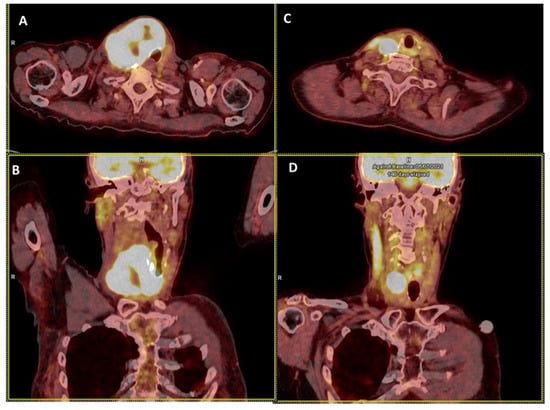

In ATC, goals of care may be therapeutic and/or palliative depending on staging and prognosis when considered in the context of available therapies, comorbidities and the patient’s wishes. Multimodal therapy refers to the combination of excisional surgery, when possible, external beam radiation therapy (EBRT), chemotherapy and/or targeted therapy (Figure 2, Figure 3 and Figure 4). This multimodal strategy is associated with a better OS in retrospective studies. In 1990, the mean OS was about two to six months [56,57] and it seems to be nearly the same 20 years later, with a one-year OS of less than 20% [58,59,60,61]. However, in a cohort of 479 patients treated in the same institution spanning nearly 20 years, Maniakas et al. found one- and two-year OS of 35/18% in the 2000/13 era (n = 227), 47/25% in the 2014/16 era (n = 100) and 59/42% in the 2017/19 era (n = 152) which suggests an impact of multi-modal treatment strategies on survival [14].

Figure 2.

Illustration of 18FDG PET/CT anaplastic thyroid carcinoma (ATC) response to chemotherapy and radiotherapy before surgery. The figure represents axial (A) and coronal (B) slices of the neck region with an ATC volume of 230 mL before initiating treatment comprising chemotherapy (Cisplatin-Doxorubicin, 2 cures) and radiotherapy (IMRT, 50 Gy. (C,D) represent axial (C) and coronal slices (D) of the neck region with an ATC volume of 15 mL.

Whenever possible, surgery must be performed as it can provide prolonged survival and even a cure in the 10% patients with stage IVa disease, in association with chemo-radiotherapy and surgery [63,65]. It should also be performed in patients with advanced disease who may respond to initial medical/radiation treatment [2,14] (Figure 2 and Figure 3).